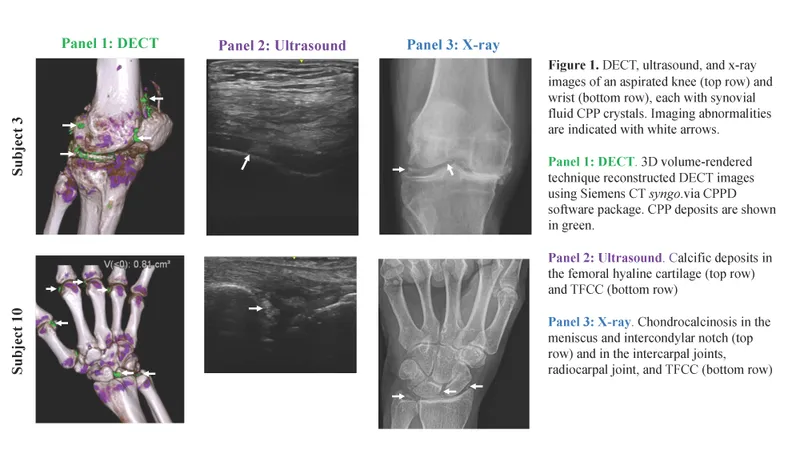

- X-ray Hallmark: Chondrocalcinosis (cartilage calcification). Common: knee, wrist, symphysis pubis.

- Diagnosis: Synovial fluid analysis: definitive, shows CPPD crystals.

- Pseudogout (CPPD): CPPD crystals (rhomboid, positively birefringent). Affects knee, wrist. Chondrocalcinosis on X-ray.